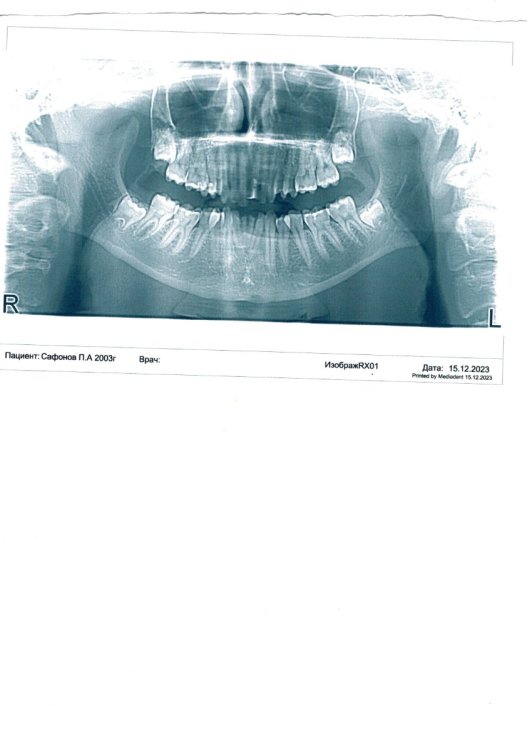

Для уточнения будет ли состояние непризывным или нет нужны: жевательная эффективность и разобщение прикуса.

“При аномалии прикуса II степени с разобщением прикуса от 5 до 10 мм с жевательной эффективностью менее 60 процентов по Н.И. Агапову или при аномалии прикуса II и III степени с разобщением прикуса более 10 мм (без учета жевательной эффективности) заключение о категории годности к военной службе выносится по пункту "б", а при аномалии прикуса II степени с разобщением прикуса от 5 до 10 мм с жевательной эффективностью 60 и более процентов - по пункту "в".”

По вашему заключение размер сагиттальной щели всего 3мм, этого может быть недостаточно.

Там же сагиттальная щель больше 3 мм . А нижняя челюсть смещена назад на 7 мм...

Лучше чтобы было указано, что это расстояние между верхней и нижней зубными дугами и тогда с вашей жевательной эффективностью будет являться основанием для списания.